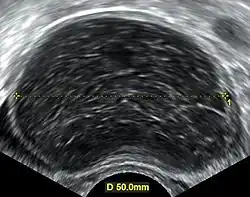

Ultrasonography Hemorrhagic Ovarian Cyst

During pregnancy, ultrasonography is the first-line method for evaluating ovarian cysts. Both transabdominal and transvaginal route of ultrasonography are used with either two-dimensional or three-dimensional modalities.[3] Two-dimensional is more common, but three-dimensional can offer more results.[3] Doppler ultrasonography can also be used and is helpful at analyzing the characteristics of the cyst.[3] It can identify the presence of color flow within a septum as well as the presence of a solid component of the mass.[3] Ultrasonography is an effective tool for observing the progression or regression of the cyst.[3] Magnetic resonance imaging (MRI) is the second-line method used when ultrasonography cannot detect the cyst.[3] Cysts that are too large to be accurately analyzed by ultrasonography are typically when MRI would be used.[3] The advantages of MRI are its larger field of view and multiplanar capabilities.[21] In addition, pathologies such as infarctions and placental invasive disorders can be seen more clearly.[3] MRI is especially beneficial in gestational age and obese people.[3] MRI is also beneficial at preventing the exposure of ionizing radiation to the fetus during pregnancy.[22] Both ultrasonography and MRI show enlarged ovaries with multiple theca lutein cysts.[3]